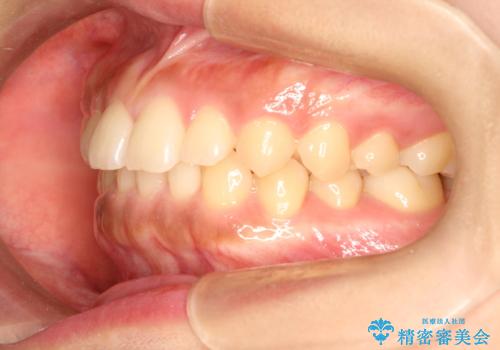

前歯の隙間を閉じたい。インビザラインによる治療

- 前歯の隙間を閉じたいと矯正カウンセリングに来られた患者様です。

マウスピース矯正(インビザライン)を行い短期間で治療が完了しました。